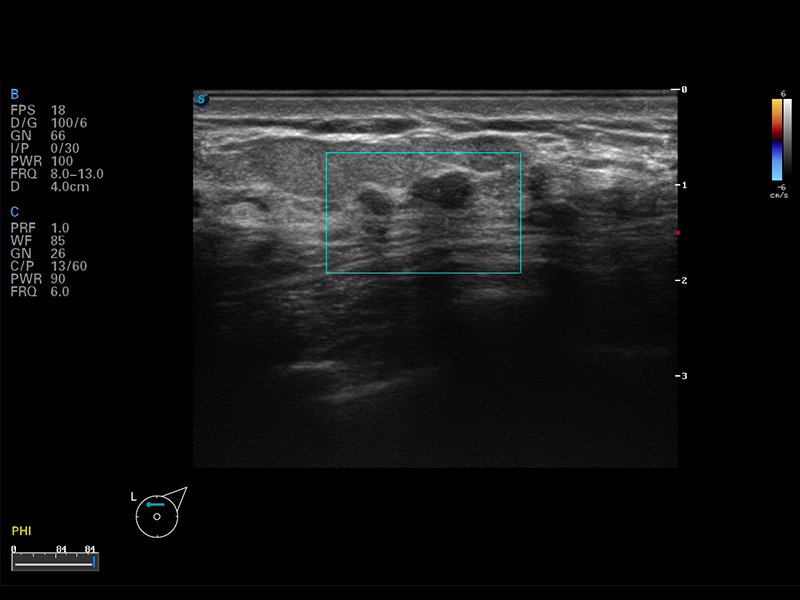

μ-Scan微米成像

空间复合成像